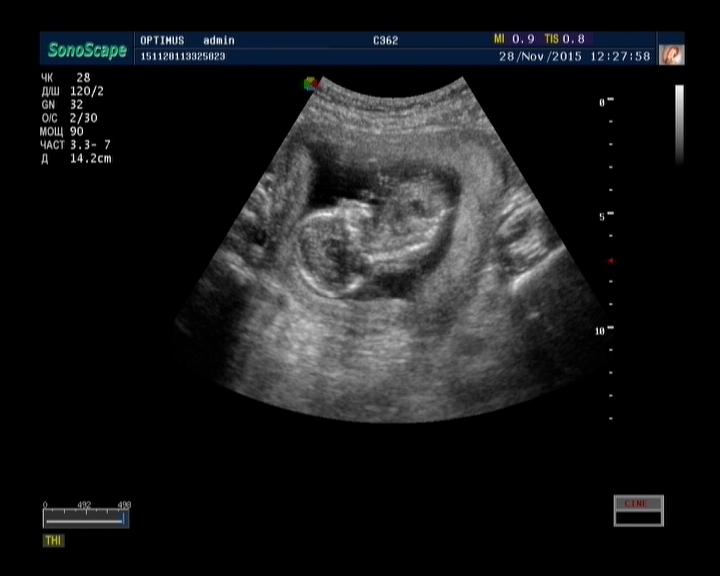

Мы ещё в новом жилом комплексе живём, все молодые, тут все или беременные или с масиками, мммм...Это же так волшебно...пиночки, узи, первая встреча с лялечкой.....

Я часто фотку достаю и любуюсь